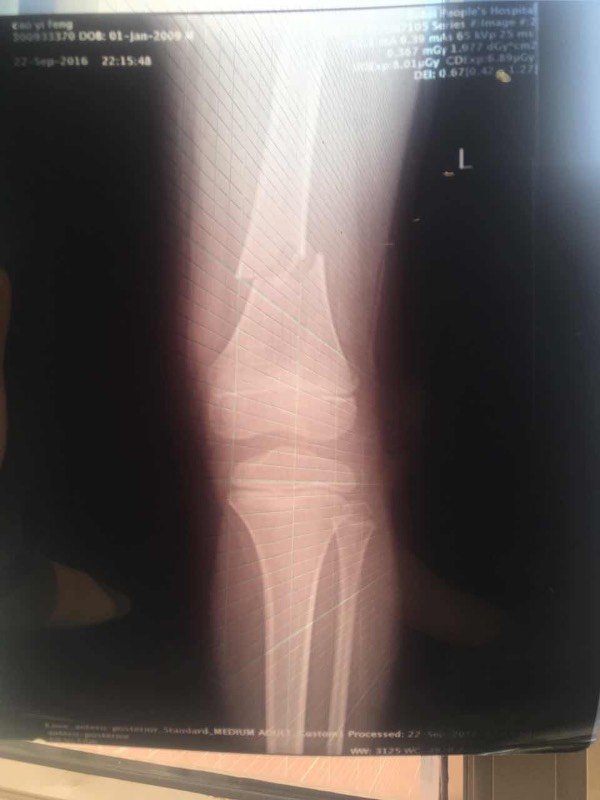

宝宝7岁,左腿股骨骨折,在南京儿童医院住院,医生建议手术治疗,但说因为小孩还会生长发育,因为骨折部位靠近膝盖,所以后期腿可能会长歪,也找人咨询过其他专家,有的说手术是首选,但也可以先试试看保守治疗,手工复位打石膏,不行再动手术,说手工复位的不可能有后遗症。有专家能给个建议吗?